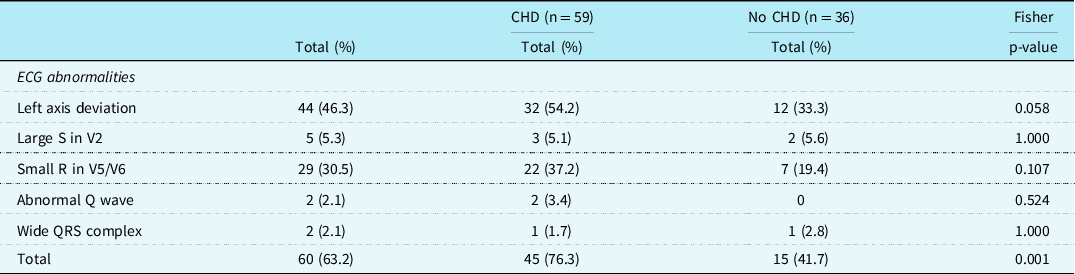

Electrographic abnormalities

In 60 patients (63.2%), one or more typical Noonan syndrome-related electrocardiographic features were seen. Most of the patients with CHD did show these typical Noonan syndrome-related electrocardiographic features (45/59, 76.3%). Also, in 15 of the 36 (41.7%) patients with a structurally normal heart on echocardiogram, typical Noonan syndrome electrocardiographic abnormalities were detected (Table 1). There was no significant difference in the incidence of the individual-specific Noonan syndrome-related electrocardiographic features between the group with CHD and the group without CHD, however, specific electrocardiographic features as a group occurred significantly more frequently in patients with CHD (p = 0.001).

There were 44 (46.3%) patients with left axis deviation, 29 (30.5%) patients with small R-waves in the left precordial leads, and 5 (5.3%) patients with large right precordial S-waves. An abnormal Q-wave was seen in 2 (2.1%) patients and a wide QRS complex also in 2 (2.1%) patients (Table 2). Typical Noonan syndrome-related electrographic features were not more often seen in patients with a mutation in the PTPN11 gene than in patients with other gene mutations. Patients with a mutation in the RAF1 gene had more frequently large S-waves in the right precordial leads (p = 0.002), and patients with SOS1 gene mutation had more frequent wide QRS complexes (p = 0.006).

Table 2. Specific ECG features in patients with Noonan syndrome with and without CHD

In this cohort, CHD was found in 62.1% and typical Noonan syndrome-related electrocardiographic features in 63.2% of Noonan syndrome patients. The typical Noonan syndrome-related electrocardiographic features were also present in 41.7% of patients without CHD. Left axis deviation was seen in 46.3% of patients, small left precordial R-waves in 30.5%, and large right precordial S-waves in 5.3% of the Noonan syndrome patients. There was no significant difference in the frequency of the individual- specific Noonan syndrome-related electrocardiographic features between the group with CHD and the group without CHD.